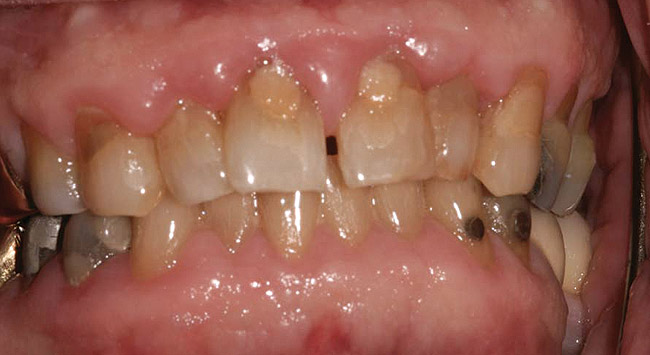

Such theories remain speculative, since it has not been possible to demonstrate whether changes in microflora are the cause or the effect of the enlargement. As noted by Modéer et al29 and Nery et al,30 plaque would act as a co-factor, since drug-induced gingival overgrowth is also observed in patients with excellent oral hygiene. Consequently, the authors concluded that rigorous plaque control in patients treated with certain drugs can limit the severity of lesion development but cannot prevent it altogether (Figure 2).

Fig 2. A 42-year-old male patient with good oral hygiene, taking 30 mg nifedipine daily, with signs of generalized gingival enlargement. (photo courtesy of Asim Alsuwaiyan, BDS)

Figure 2